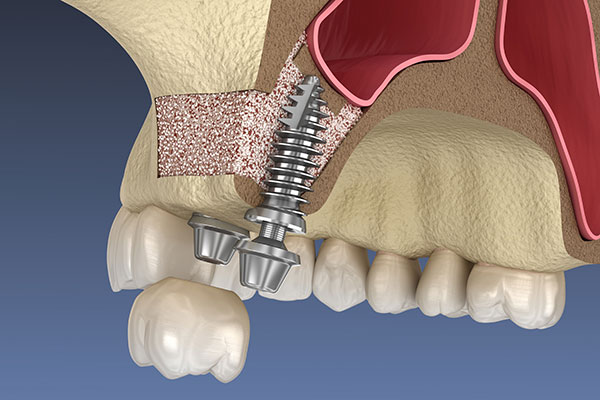

上顎の難症例

上顎の奥歯の上部には「上顎洞(服鼻腔)」という空洞があり、骨が極めて薄いケースが多く見られます。このような難症例に対しては、上顎洞の底を押し上げて骨を作る「サイナスリフト」や「ソケットリフト」に対応しています。口腔外科的な知見に基づき、安全な手法を選択。高度な外科処置を伴いますが、精密な事前診断のもと、安定したインプラント治療が行える環境を整えます。